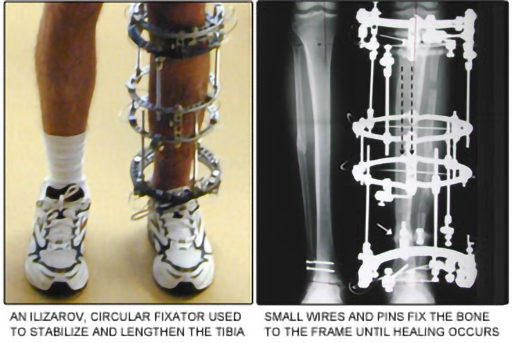

Can hormones, drugs and surgical intervention prevent bone loss or encourage bone formation? In the 1940s, Russian scientists developed a surgical technique for promoting bone growth. They found that inserting screws into the bones and gradually forcing the bones apart promotes bone growth (Figure 5).